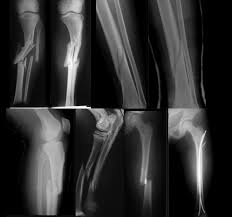

pada pemeriksaan di radiologi tidak semua pasien yang datang untuk foto rontgen dalam ke adaan yang umum atau 'normal' 'terkadang kita dihadapkan dengan situasi dengan pasien yang tidak biasa atau 'tidak normal' tetapi disinilah salah satu tantangan dalam menghadapinya , mungkin ini beberapa contoh kasus yang tidak biasanya..